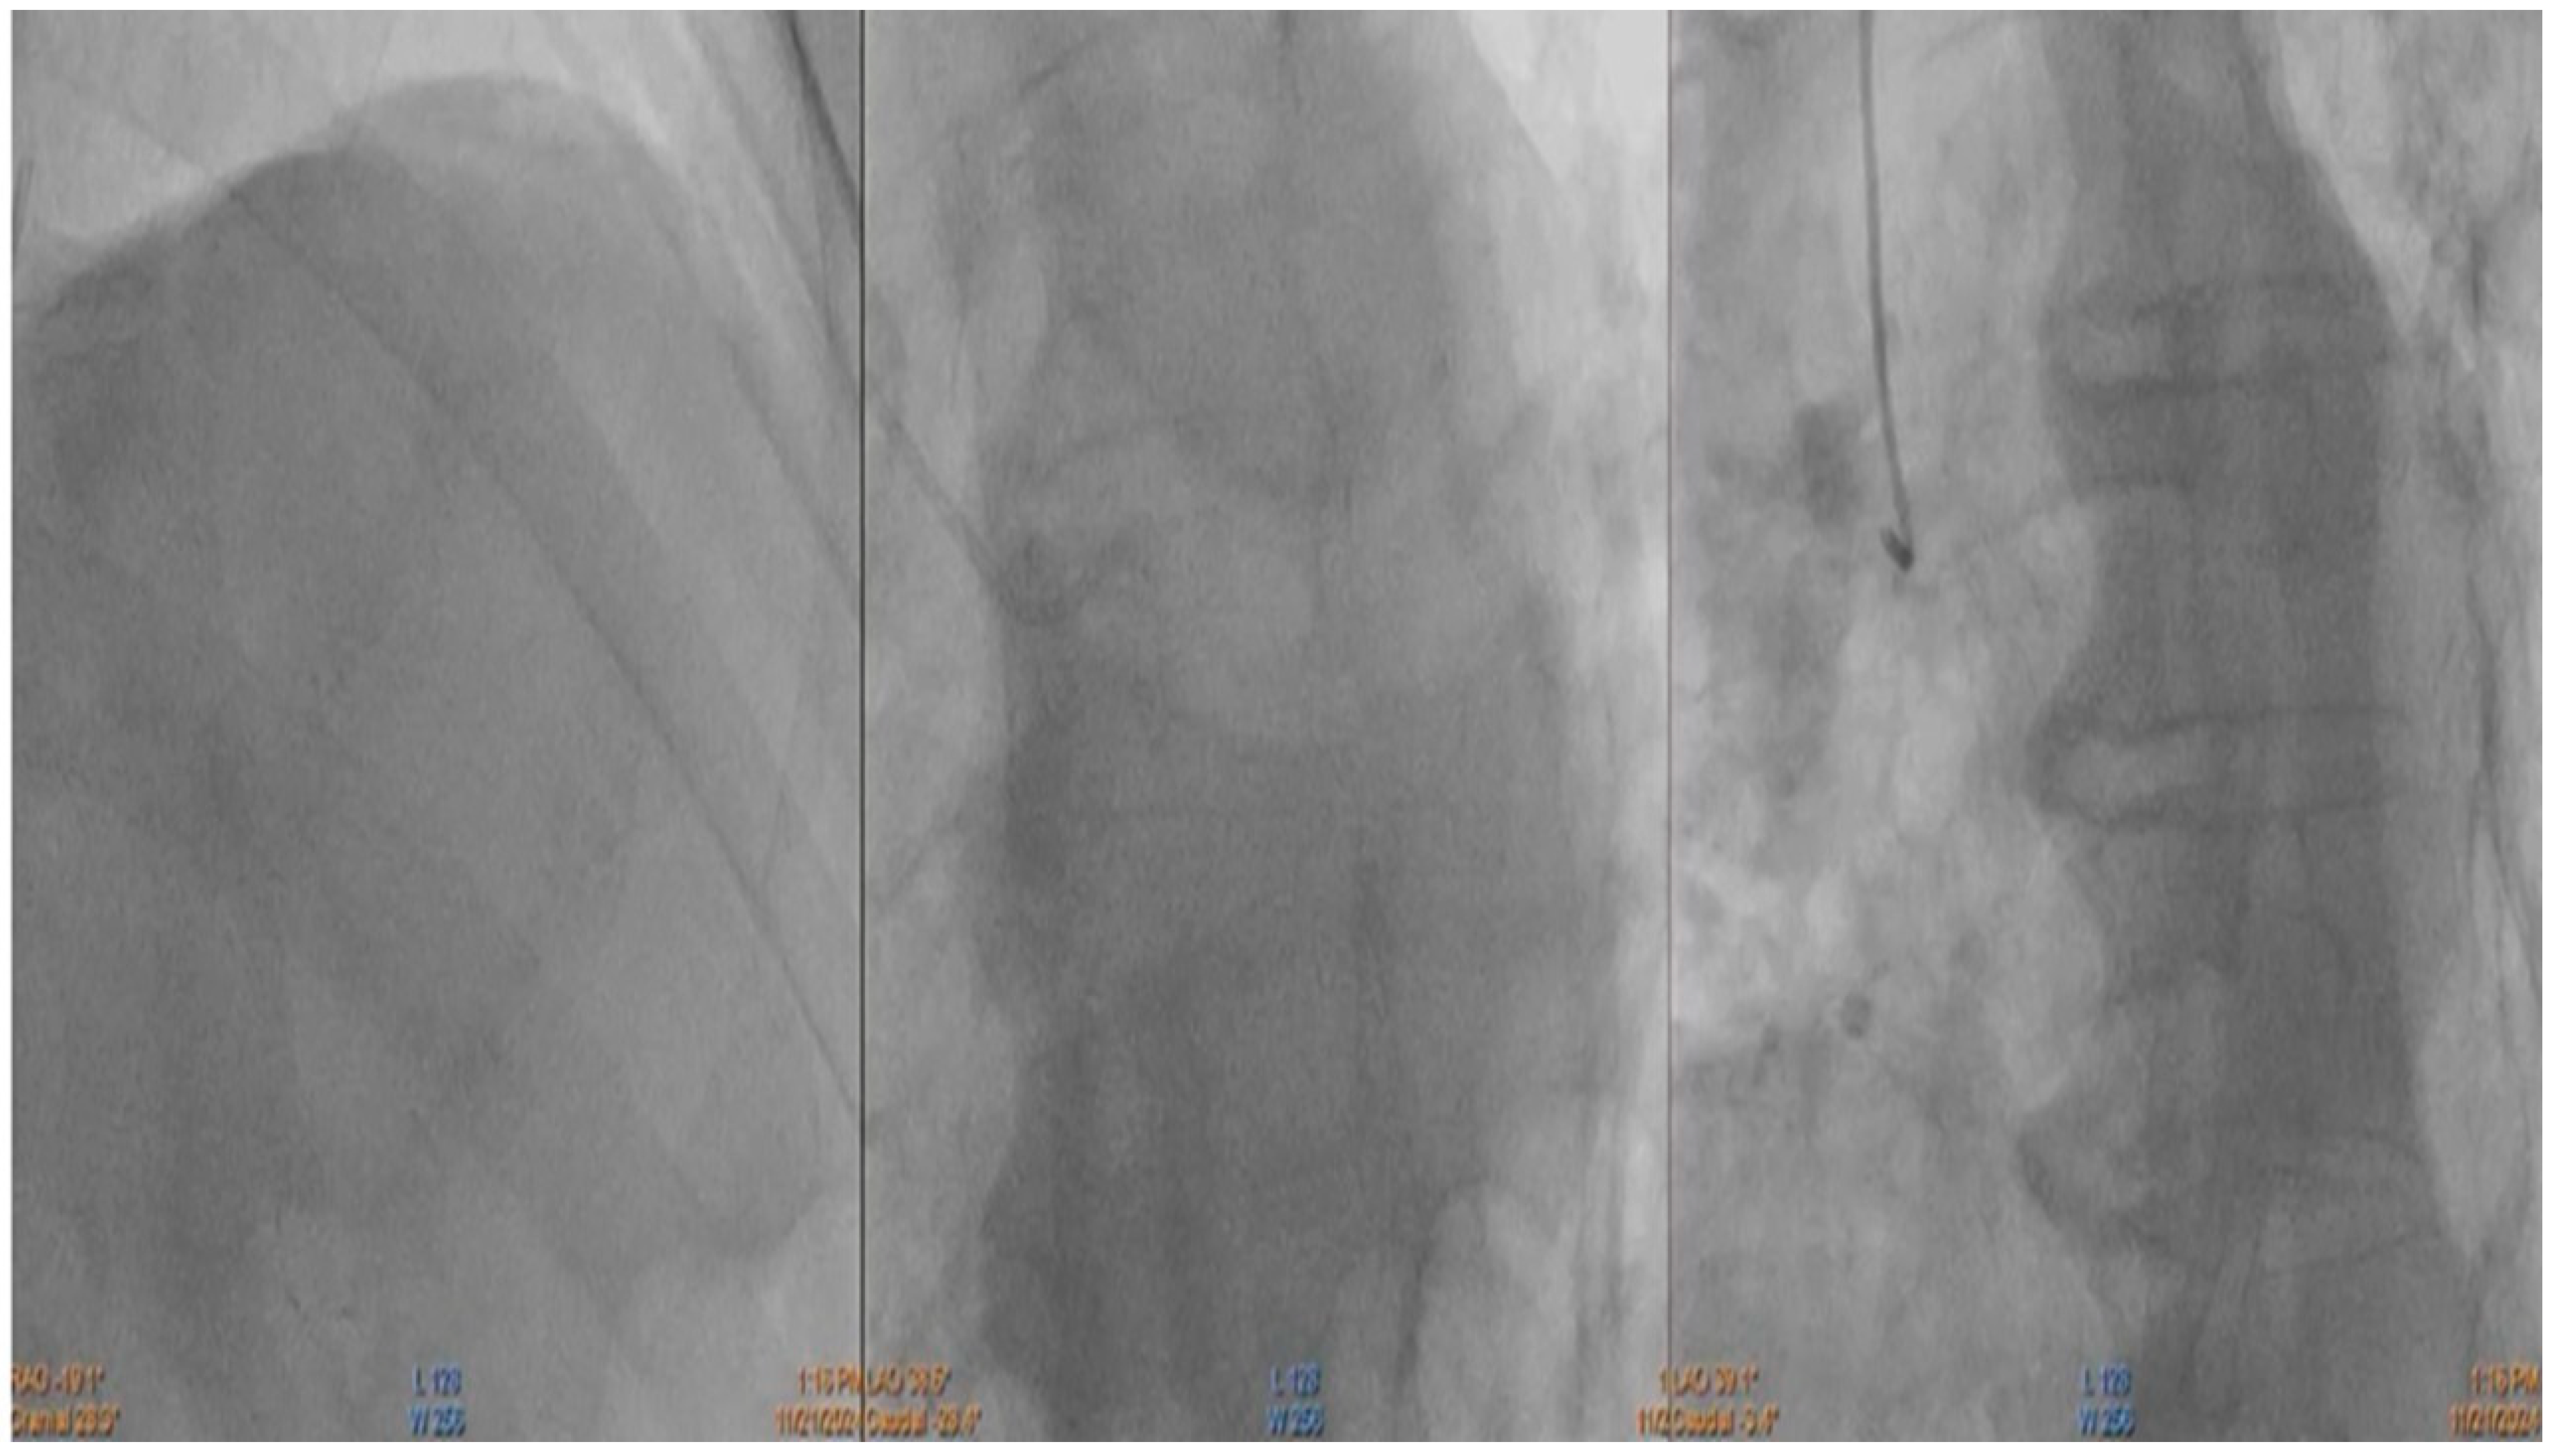

2. Detailed Case Description